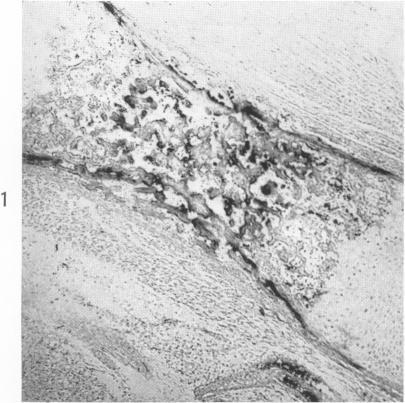

The demonstration of iron in osseous tissue by Fe59 radioautography.

Am J Pathol. 1963 Mar;42(3):285-91.